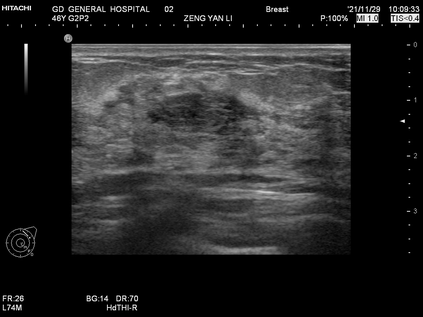

Ultrasonography is an important routine examination for breast cancer diagnosis, due to its non-invasive, radiation-free and low-cost properties. However, it is still not the first-line screening test for breast cancer due to its inherent limitations. It would be a tremendous success if we can precisely diagnose breast cancer by breast ultrasound images (BUS). Many learning-based computer-aided diagnostic methods have been proposed to achieve breast cancer diagnosis/lesion classification. However, most of them require a pre-define ROI and then classify the lesion inside the ROI. Conventional classification backbones, such as VGG16 and ResNet50, can achieve promising classification results with no ROI requirement. But these models lack interpretability, thus restricting their use in clinical practice. In this study, we propose a novel ROI-free model for breast cancer diagnosis in ultrasound images with interpretable feature representations. We leverage the anatomical prior knowledge that malignant and benign tumors have different spatial relationships between different tissue layers, and propose a HoVer-Transformer to formulate this prior knowledge. The proposed HoVer-Trans block extracts the inter- and intra-layer spatial information horizontally and vertically. We conduct and release an open dataset GDPH&GYFYY for breast cancer diagnosis in BUS. The proposed model is evaluated in three datasets by comparing with four CNN-based models and two vision transformer models via a five-fold cross validation. It achieves state-of-the-art classification performance with the best model interpretability.